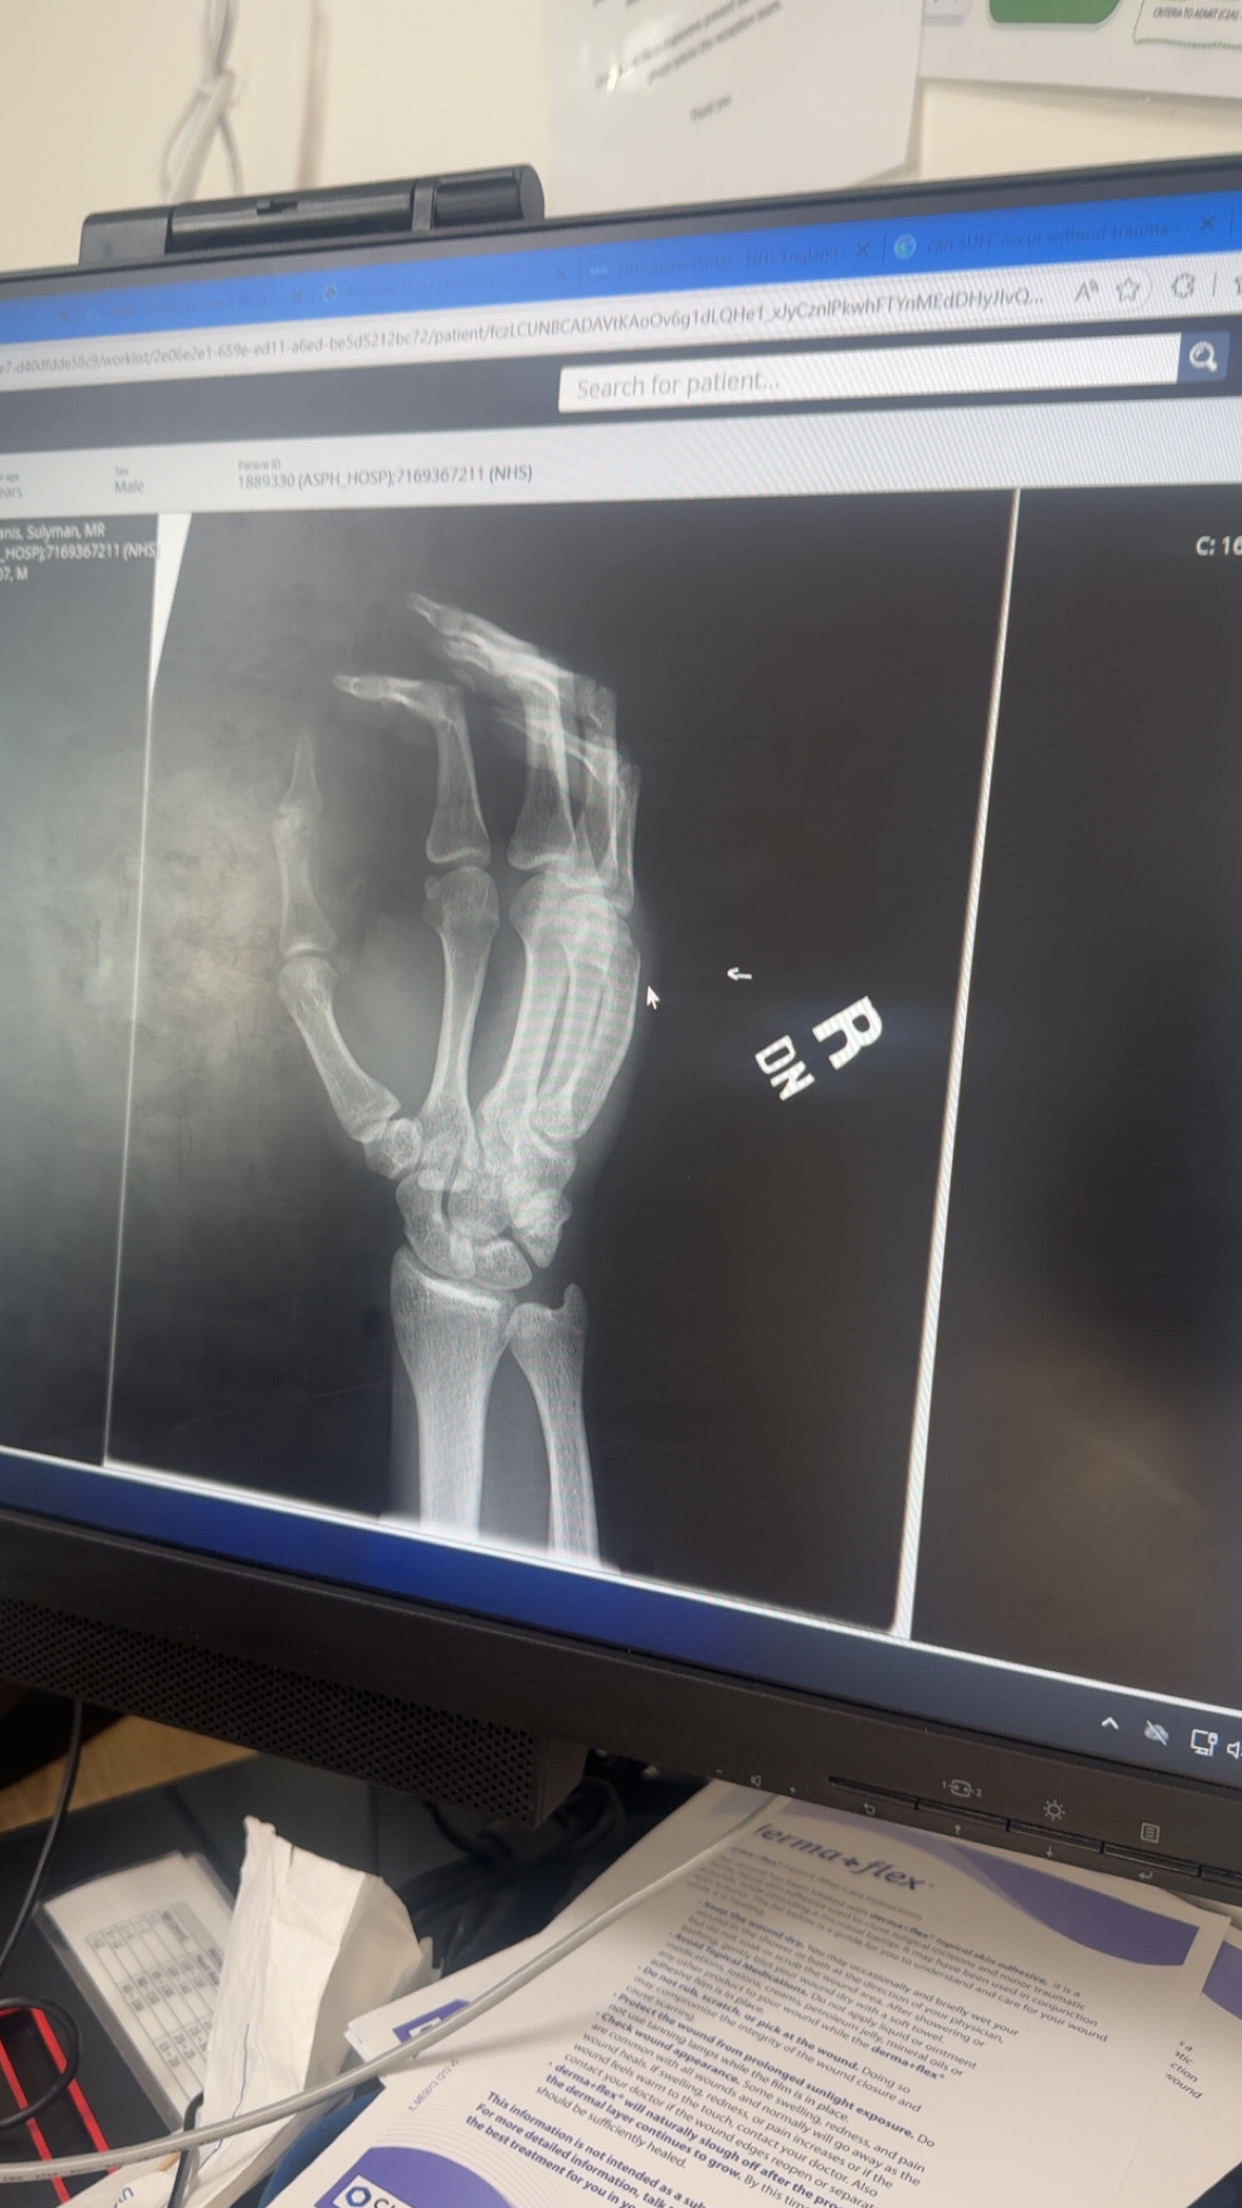

Bone age x ray

IMG 2304

Second picture u can slightly see wrist, fully closed

yh gemini said fully closed and gpt and claude said not fully closed yet but close. heard hands fuse before elbows and legs so i may b able to squeeze an inch or 2 and get to like 6'1 w tha hgh im taking. If not idrc tm either tho